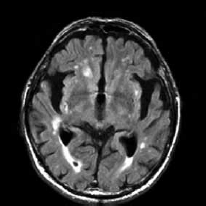

Paciente de 72 anos é referida ao consultório neurológico com queixas progressivas de perda de memória, alterações no comportamento e dificuldade em realizar tarefas diárias complexas, observadas pela família nos últimos dois anos. A avaliação cognitiva estruturada revela déficits significativos na memória episódica, funções executivas e orientação visuoespacial. O exame neurológico é notável por marcha apráxica e presença leve de rigidez axial. A ressonância magnética (RM) encontra-se a seguir.

Enunciado 4100213-1

Com base nesses achados clínicos e radiológicos, das seguintes condições, assinale a que representa, corretamente, o diagnóstico mais provável.